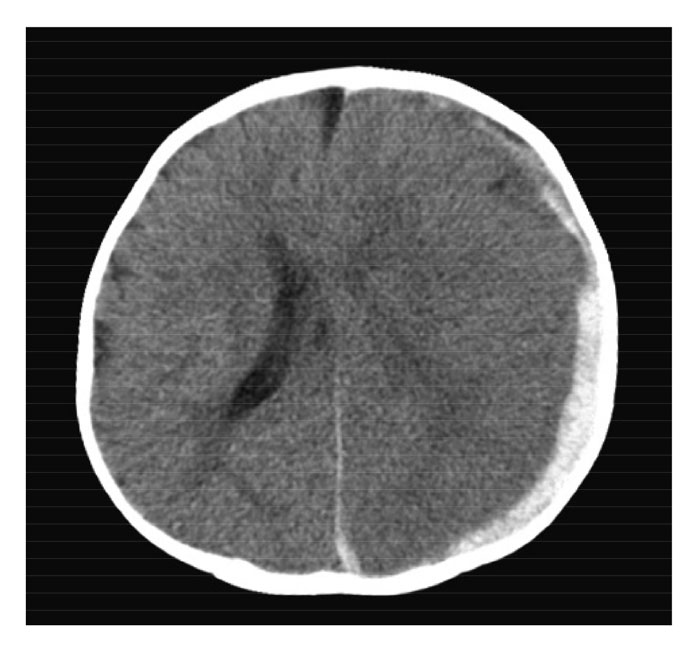

Aちゃん(生後4か月、女児)は、嘔吐とけいれんのため病院を受診した。

受診時、Aちゃんは傾眠状態で、顔色不良と眼球上転がみられたため入院となった。

受診時の体温は36.8℃であった。四肢は硬直し、数か所の内出血斑があった。

大泉門は平坦であったが、次第に膨隆を認めるようになった。

このときの頭部CTを別に示す。

Aちゃんの所見として考えられるのはどれか。